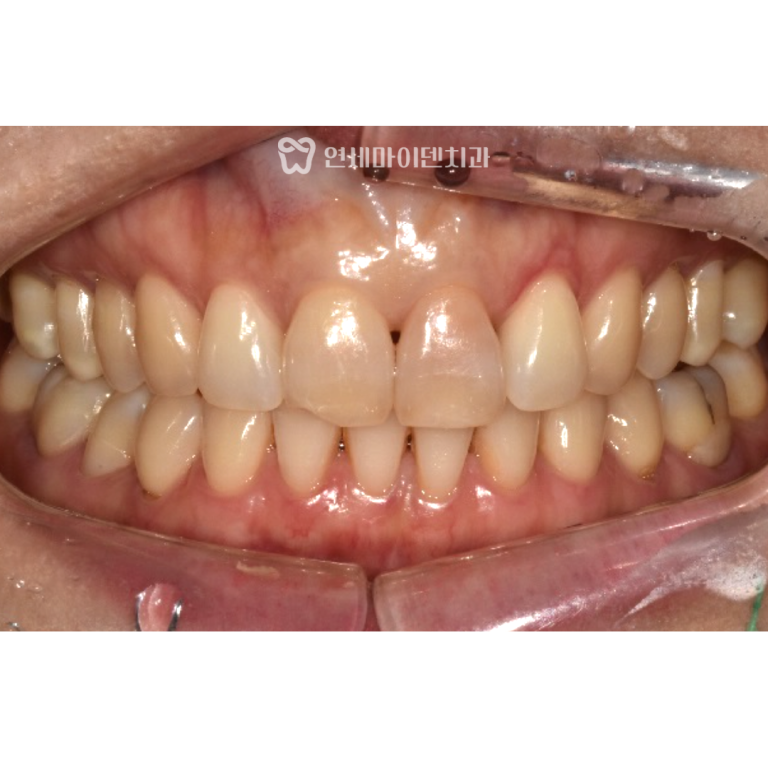

발치 직전까지 갔던 치아는

재신경치료

지르코니아 보철로 마무리되었고,

현재까지도 문제 없이

잘 사용하고 있습니다.